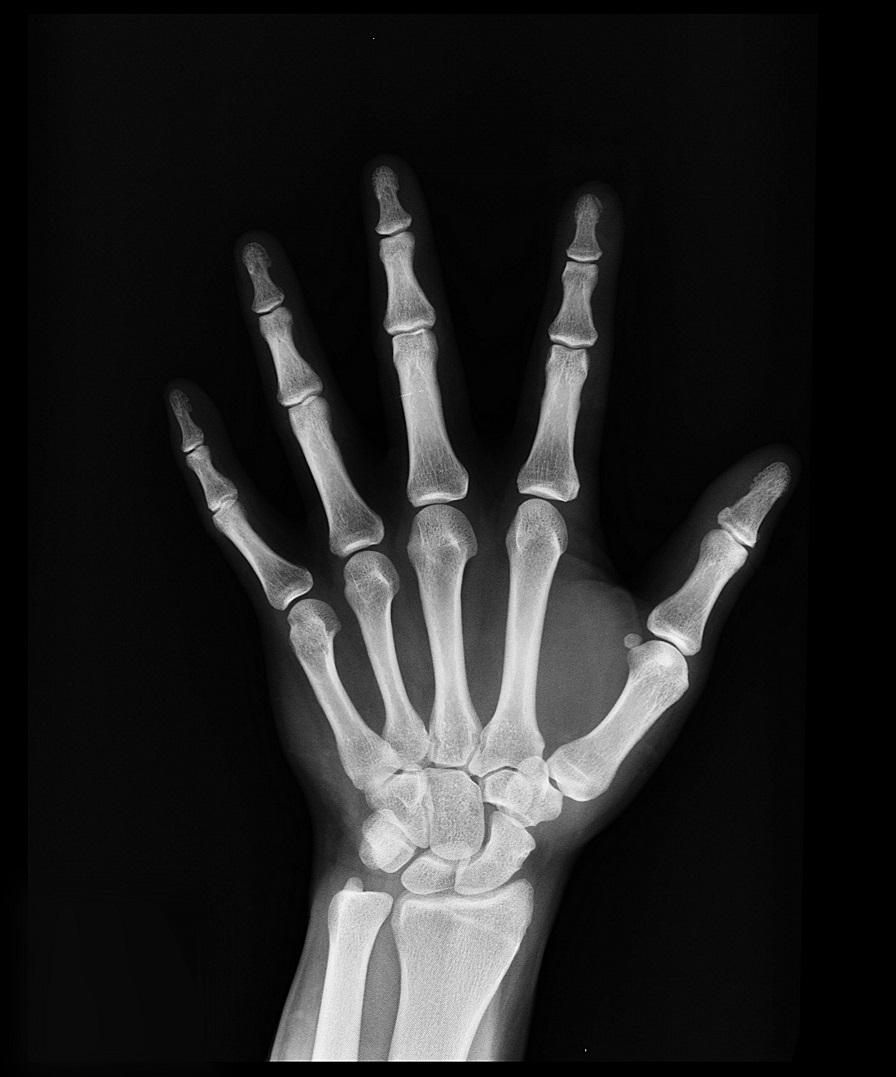

También se solicita una radiografía de muñeca que nos ayuda a ver el grado de maduración ósea y se compara con un atlas con radiografías de otros niños de la misma edad.

En el chico la pubertad retrasada es más frecuente que en la chica, y su causa más frecuente es el retraso constitucional del crecimiento y desarrollo. En muchas ocasiones se acompaña de un crecimiento lento previo y una edad ósea (radiografía de muñeca) retrasada. Suele haber antecedentes en el padre y/o hermanos.